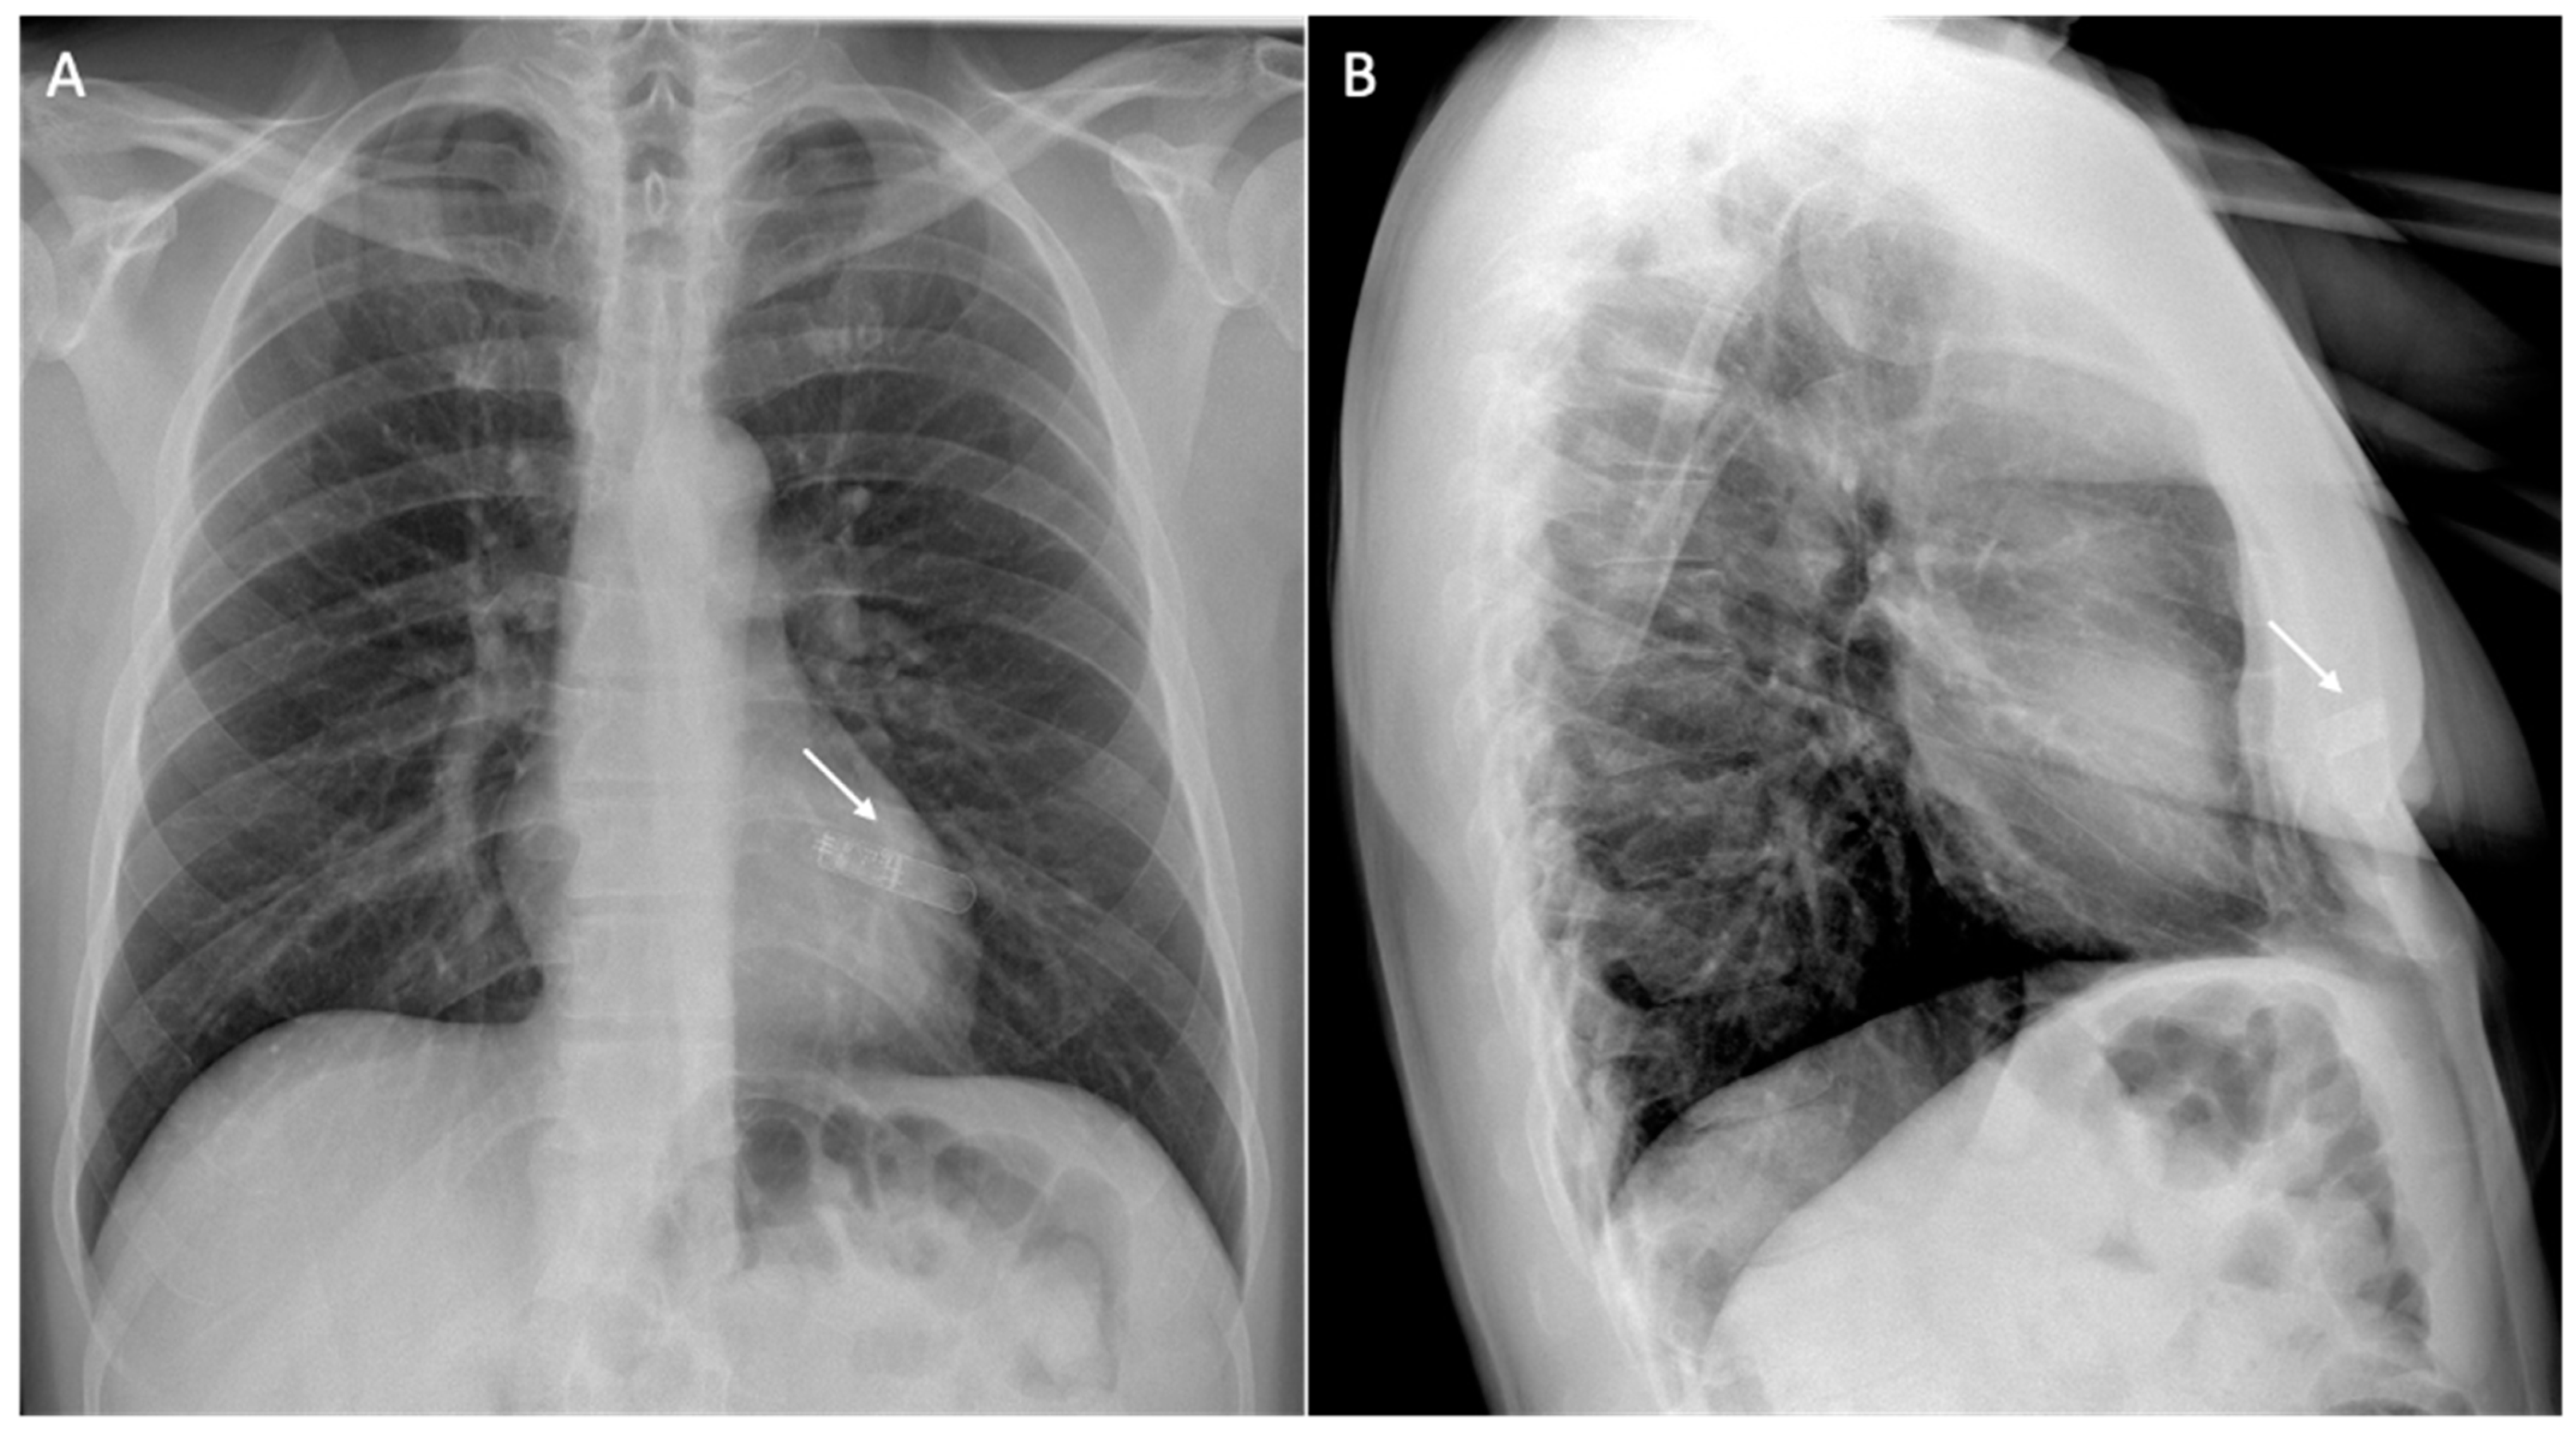

6. Issue: Artifact

- Vuorinen, A.-M.; Lehmonen, L.; Karvonen, J.; Holmström, M.; Kivistö, S.; Kaasalainen, T. Reducing cardiac implantable electronic device–induced artefacts in cardiac magnetic resonance imaging. Eur. Radiol. 2022, 33, 1229–1242. [Google Scholar] [CrossRef] [PubMed]

| Types of Artifacts | Factors that Influence Artifacts | High Artifact | Low Artifact |

|---|---|---|---|

| Signal loss artifact Hyperintensity artifact | CIED’s dimension | Large device | Small device |

| CIED’s position | Left-sided implantation | Right-sided implantation | |

| Magnetic susceptibility | High ferromagnetic component | Low ferromagnetic components | |

| High static MF | Low static MF | ||

| Distance from the region of interest | Proximity to the heart | Elevate the patient’s arm | |

| MRI sequences used | Cine SSFP | SGE sequences | |

| LGE sequence with a bandwidth of about 1 kHz | LGE sequence with a wide bandwidth |